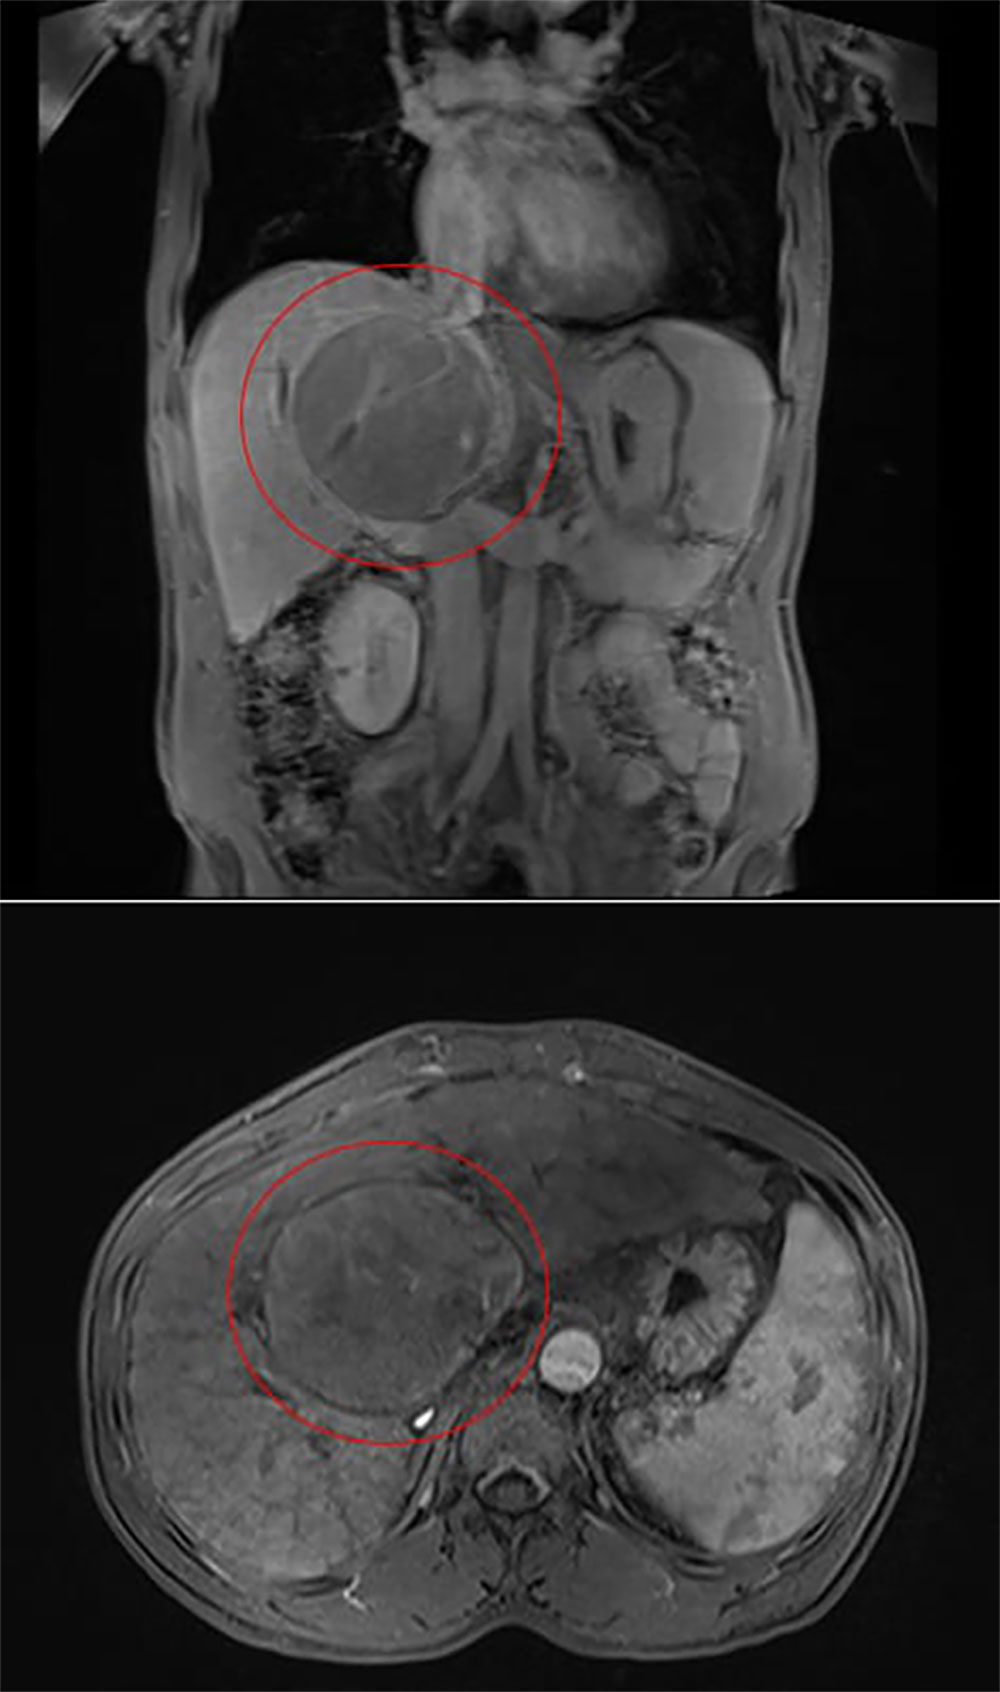

وعليه، أظهر كشف الفحوصات، بما في ذلك فحص التصوير بالرنين المغناطيسي والخزعة، عن وجود سرطان الخلايا الكبدية، وهو ورم كبدي أولي بحجم 9 سم موجود بالقرب من مركز الكبد. وكان للمريض تاريخ مرضي من التهاب الكبد المزمن B، والذي أدى على الأرجح إلى تليف الكبد مما عقَّد خيارات العلاج. عادةً ما تتطلب الحالات التي تنطوي على أورام تقع بالقرب من الأوعية الدموية الرئيسية تدابير جراحية مثل استئصال الكبد. ومع ذلك، في هذه الحالة، فإن حجم الورم وحالة تليف الكبد المتقدمة للمريض (المستوى ب) جعلت هذه الخيارات أكثر خطورة.